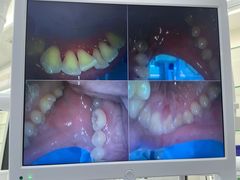

• -牙博士口腔品牌连锁(杨浦店)

夏日莫莫茶 | 21-08-13